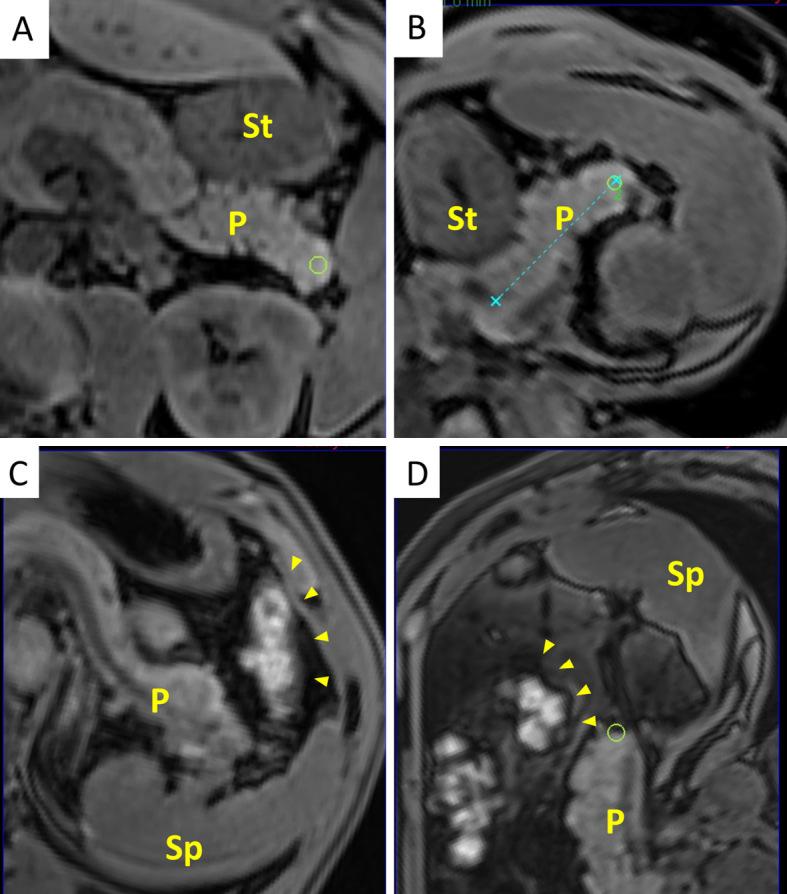

Objective Abdominal ultrasonography (AUS) is used to screen for abdominal diseases owing to its low cost, safety, and accessibility. However, the detection rate of pancreatic disease using AUS is unsatisfactory. We evaluated the visualization area of the pancreas and the efficacy of manipulation techniques for AUS with fusion imaging. Methods Magnetic resonance imaging (MRI) volume data were obtained from 20 healthy volunteers in supine and right lateral positions. The MRI volume data were transferred to an ultrasound machine equipped with a fusion imaging software program. We evaluated the visualization area of the pancreas before and after postural changes using AUS with fusion imaging and assessed the liquid-filled stomach method using 500 ml of de-aerated water in 10 randomly selected volunteers. Patients This study included 20 healthy volunteers (19 men and 1 woman) with a mean age of 33.0 (21-37.5) years old. Results Fusion imaging revealed that the visualization area of the entire pancreas using AUS was 55%, which significantly improved to 75% with a postural change and 90% when using the liquid-filled stomach method (p=0.043). Gastrointestinal gas is the main obstacle for visualization of the pancreas. Conclusion Fusion imaging objectively demonstrated that manipulation techniques can improve pancreatic visualization.